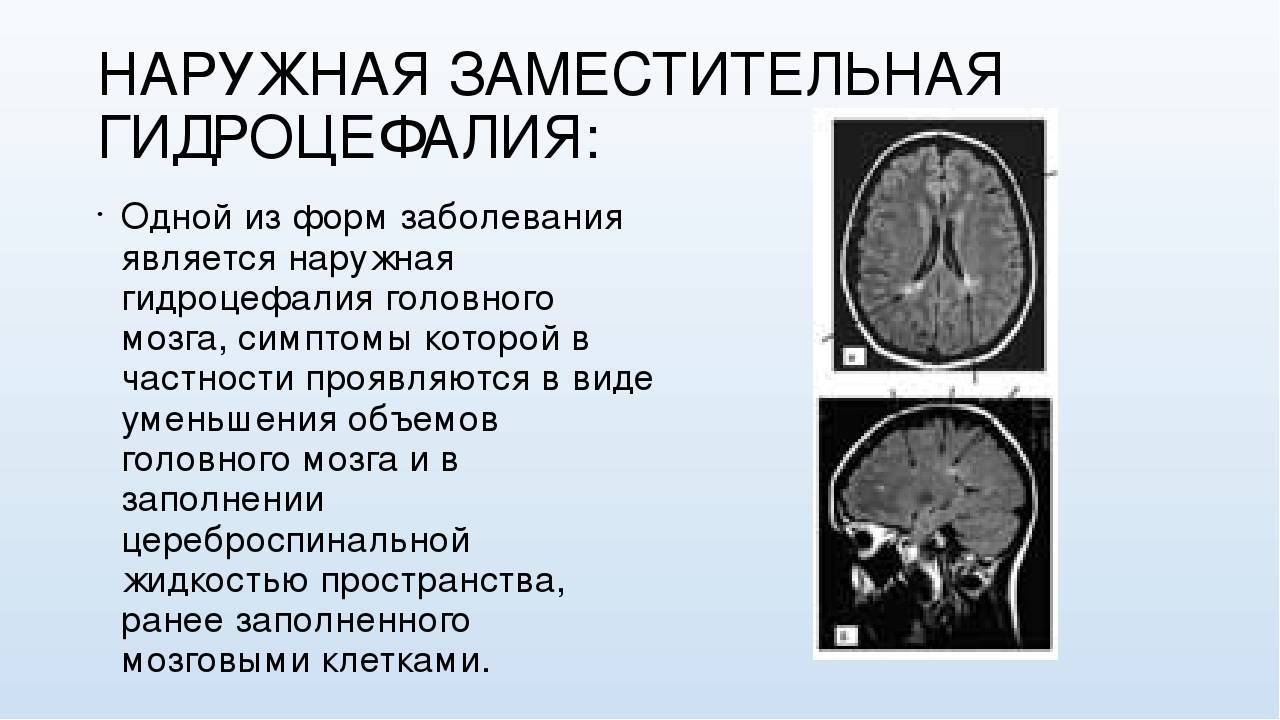

Признаки умеренно выраженной наружная

Признаки умеренно выраженной наружная 113 фото